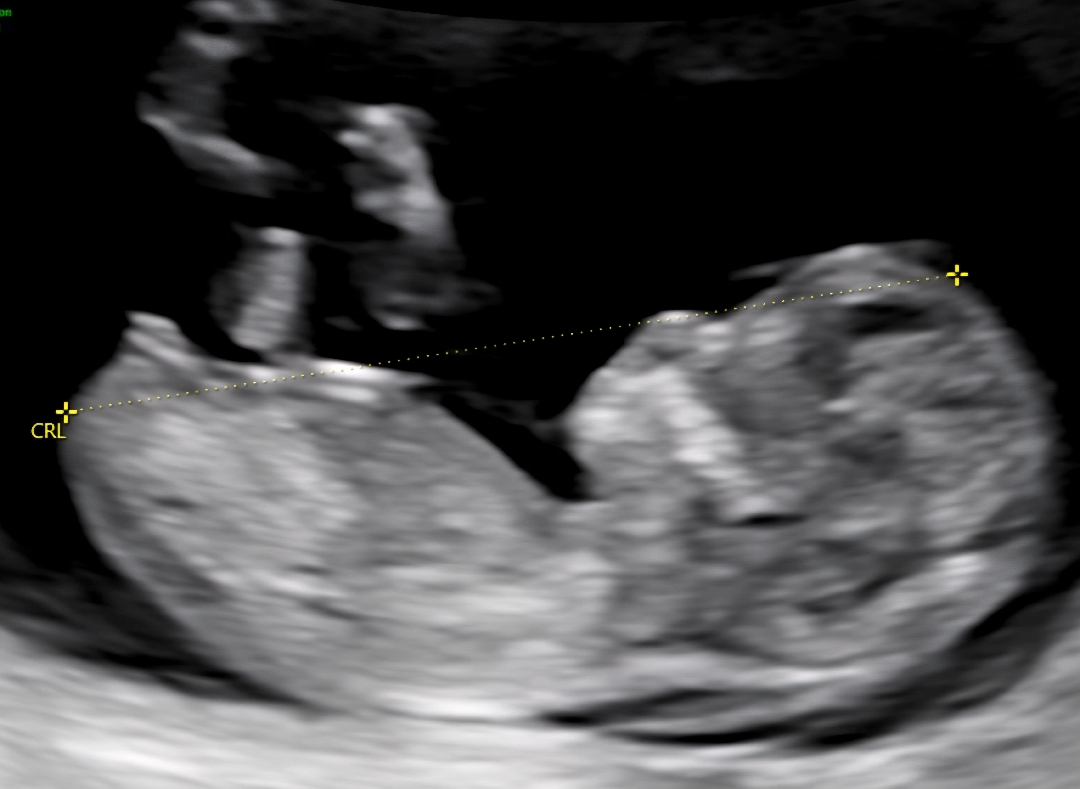

11주5일 성별 각도법 참견해주세요

아가 성별 각도법 딸일까요? 아들일까요?